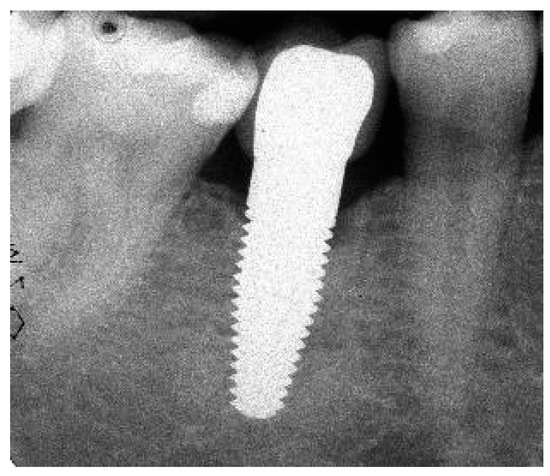

Figure 1.

(a) Exemplary radiograph at the 5-year follow-up depicting a single-tooth implant with a distinct vertical defect at the mesial and distal aspect of the implant. The lower corner of the straight cylindrical implant part was used as reference point for bone level calculations. (b) Clinical situation of the same implant prior to removal.

3.3. Marginal Bone Remodelling

From implant insertion (II) to PI, the mean marginal bone loss was 1.13 mm and from II to the 1-year follow-up it was 1.31 mm. A bone loss of 1.45 mm between II and the 3-year follow-up and of 1.12 mm between II and the 5-year follow-up was found. The results indicate that there was a slight further increase in bone loss from the 1-year to the 3-year follow-up but a decrease in bone loss from the 3-year to the 5-year follow-up (Table 7). At the 5-year follow-up, at 11 of 41 eligible implants (27%), a marginal bone loss of more than 2 mm was detected. Of these 11 implants, 5 demonstrated more than 3 mm of bone loss. This resulted in a 73% success grade I and to 88% success grade II after 5 years [26]. An exemplary radiograph and clinical picture show the typical bone loss pattern (Figure 1). Regarding any influence or correlation of baseline parameters, the performed univariate analysis did not disclose any effect or correlation of these parameters onto the bone remodelling/loss from implant insertion to the 5-year follow-up (Table 8).